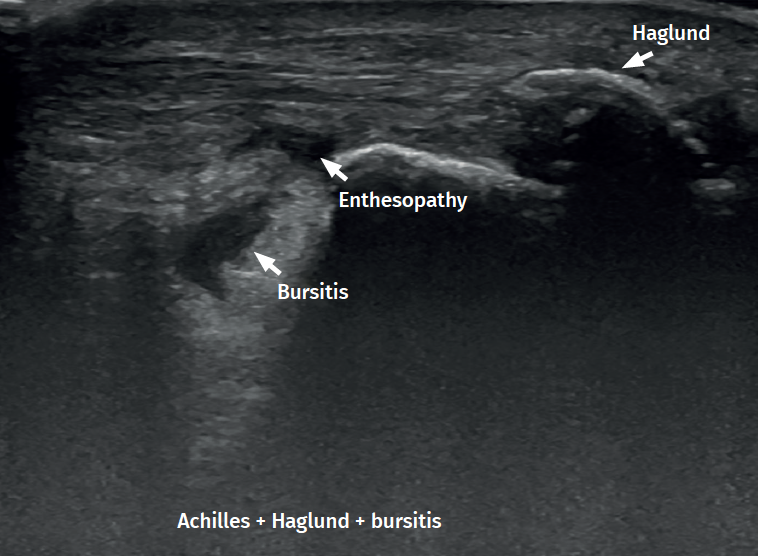

Figure 1. Insertional Achilles tendinopathy associated to retroachilleal bursitis and Haglund deformity.

With regard to the pathological ultrasound findings (Table 1), non-insertional Achilles tendinopathy (2-6 cm from the calcaneal insertion) (Figure 1) is characterized by a spindle-form thickening of the tendon area, hypoechoic areas and disruption of the fibrillar pattern that can correspond to degeneration or partial rupture(24,28). Increased vascularization of the peritendinous ventral portion may also be present(5,6,30).

However, in the chronic forms of insertional Achilles tendinopathy or enthesopathy (present in the distal 2 cm of the tendon), we can observe calcifications within the tendon in the form of traction enthesophytes or at the insertion site in the form of spurs. These conditions are often associated to alterations of the retroachilleal bursa(5,31)(Figure 2).

Retrocalcaneal bursitis is characterized by an increased volume of the bursa, with the possible association of Haglund deformity(25). In the case of retroachilles or superficial calcaneal bursitis we can identify fluid between the skin and the Achilles tendon(5).